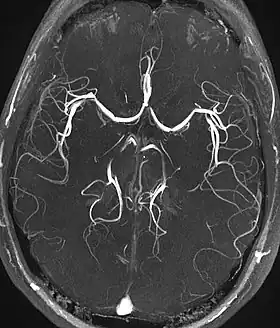

Magnetic resonance angiography (MRA) generates pictures of the arteries to evaluate them for stenosis (abnormal narrowing) or aneurysms (vessel wall dilatations, at risk of rupture). MRA is often used to evaluate the arteries of the neck and brain, the thoracic and abdominal aorta, the renal arteries, and the legs (called a "run-off"). A variety of techniques can be used to generate the pictures, such as administration of a paramagnetic contrast agent (gadolinium) or using a technique known as "flow-related enhancement" (e.g., 2D and 3D time-of-flight sequences), where most of the signal on an image is due to blood that recently moved into that plane (see also FLASH MRI).[53]

Techniques involving phase accumulation (known as phase contrast angiography) can also be used to generate flow velocity maps easily and accurately. Magnetic resonance venography (MRV) is a similar procedure that is used to image veins. In this method, the tissue is now excited inferiorly, while the signal is gathered in the plane immediately superior to the excitation plane—thus imaging the venous blood that recently moved from the excited plane.[54]

| Magnetic resonance angiography (MRA) and venography | Time-of-flight | TOF | Blood entering the imaged area is not yet magnetically saturated, giving it a much higher signal when using short echo time and flow compensation. | Detection of aneurysm, stenosis, or dissection[94] | ![]() |